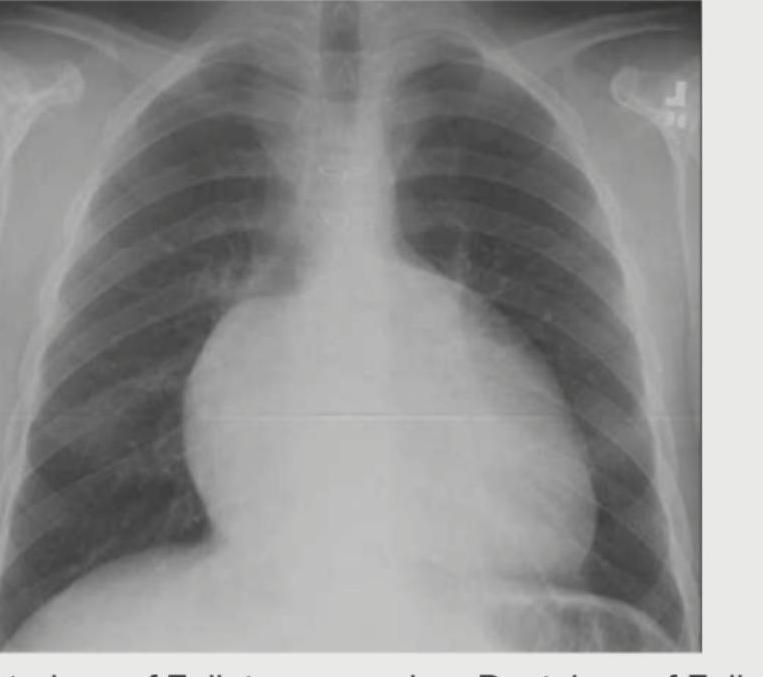

Question 4: A 30-year-old hypertension patient presents with daily headaches. The CXR given below shows which of the following? (Recent NEET Pattern 2016-17)

- B. Postductal coarctation (Correct Answer)

Explanation: ***Postductal coarctation*** - The image shows **rib notching** (highlighted by the arrow), a classic sign of **collateral vessel development** due to narrowing of the aorta **distal to the ductus arteriosus**. - This congenital heart defect is associated with **hypertension** in the upper extremities and can lead to symptoms like **headaches**. *Preductal coarctation* - This typically presents earlier in life, often with **heart failure** in infancy, and is less commonly associated with **hypertension** and **rib notching** in a seemingly asymptomatic adult. - The coarctation is located **proximal to the ductus arteriosus**, leading to different collateral circulation patterns. *Aortic dissection* - This condition is an acute medical emergency characterized by a tear in the **aortic wall**, often presenting with sudden, severe chest or back pain. - CXR findings typically include a **widened mediastinum**, not specifically rib notching. *Takayasu arteritis* - This is a **granulomatous vasculitis** primarily affecting the aorta and its major branches, leading to narrowing or occlusion. - While it can cause hypertension, **rib notching** is not a characteristic radiological finding; signs usually include vessel wall thickening or stenoses.